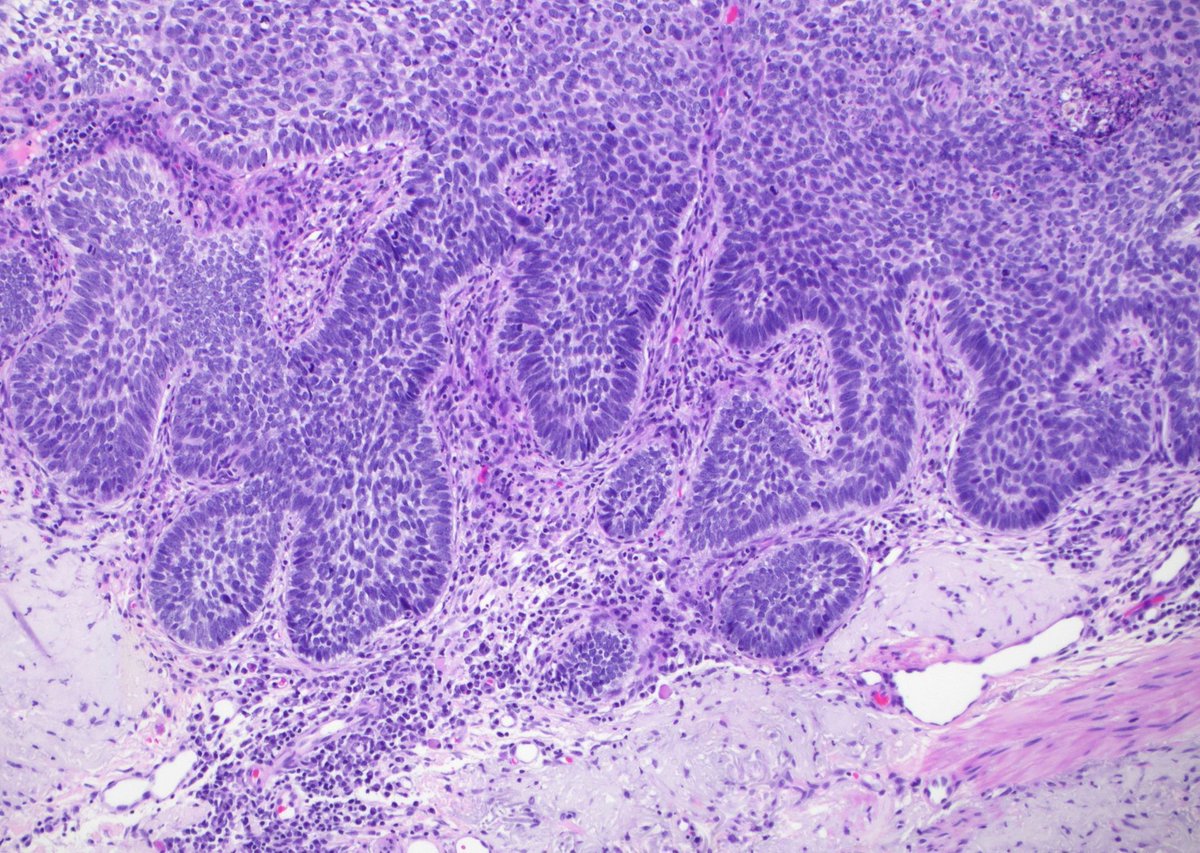

20 yo F. Bilateral groin excisions. Diagnosis? Digital slides: kikoxp.com/posts/8027 Answer ✅ youtu.be/Zy07nO1VuiY?si… #pathology #pathologists #pathTwitter #dermpath #dermatology #dermatologia #dermtwitter

20 yo F. Bilateral groin excisions. Diagnosis?

Digital slides: kikoxp.com/posts/8027

Answer ✅ youtu.be/Zy07nO1VuiY?si…